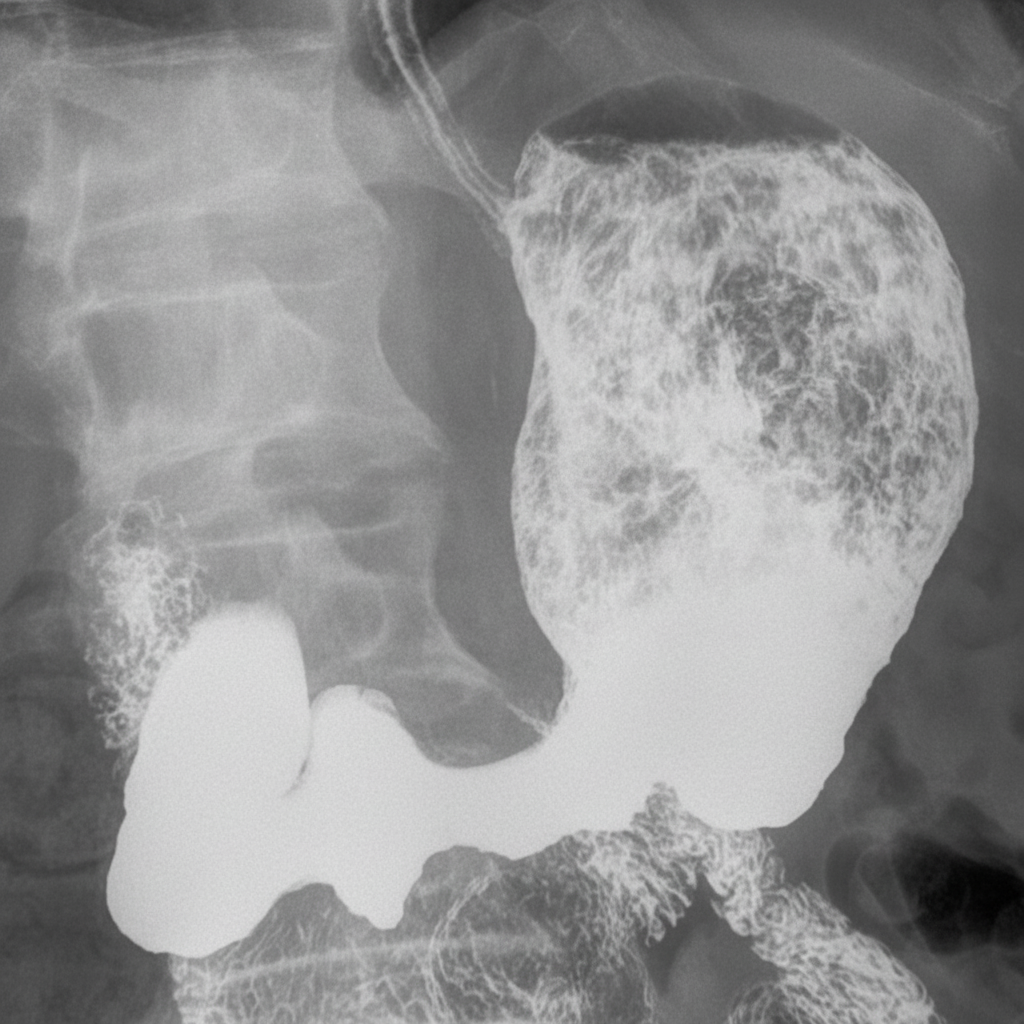

Following is an upper GI contrast study. What is the probable diagnosis?

Explanation: ***Gastric carcinoma*** - Upper GI contrast studies in gastric carcinoma show characteristic **filling defects** with **irregular mucosal surfaces** and **shouldering** at the margins of the lesion. - Advanced cases may demonstrate **linitis plastica** (leather bottle stomach) with rigid, non-distensible gastric walls and loss of normal rugal folds. *Gastric ulcer* - Benign gastric ulcers typically show **Hampton's line** (thin radiolucent line at the neck of the ulcer crater) and **smooth, regular edges**. - The ulcer crater **projects outside the expected gastric lumen** with surrounding edematous but otherwise normal mucosa. *Duodenal ulcer* - Most commonly occurs in the **duodenal bulb** and appears as a **contrast-filled crater** with smooth, round margins. - Associated findings include **duodenal bulb deformity** and **pyloric spasm**, but would not present as a gastric filling defect. *Duodenal perforation* - Would show **free contrast extravasation** into the peritoneal cavity, particularly in the **right paracolic gutter**. - Clinical presentation includes **acute severe abdominal pain** and **peritoneal signs**, not consistent with a routine upper GI contrast study finding.